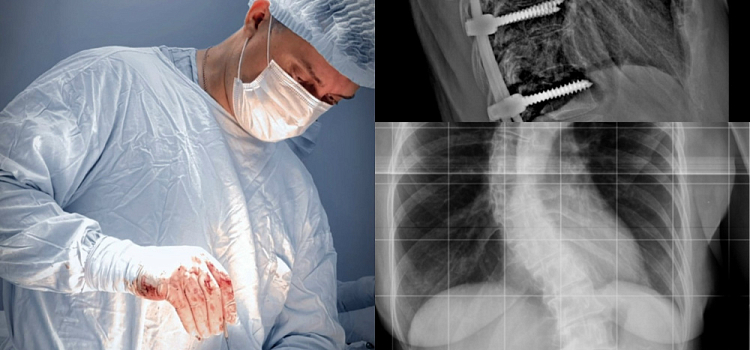

57-летняя женщина жила с невыносимой болью. Её позвоночник напоминал латинскую букву S, а на спине сформировался рёберный горб — всё это не позволяло полноценно жить. Этой историей поделились в больнице им. Н. В. Соловьёва.

За дело взялся ведущий специалист региона по сложнейшим патологиям позвоночника — заведующий 3-м нейрохирургическим отделением Владимир Герасимов. Осмотрев женщину, он принял решение: нужна сложнейшая операция по коррекции сколиотической деформации.

В операционной все решилось за три с половиной часа. Хирурги установили пациентке 18-винтовую металлоконструкцию — настоящий инженерный шедевр, который буквально выпрямил и зафиксировал позвоночник в правильном положении.

«Нам удалось скорригировать ось позвоночника, — прокомментировал Владимир Герасимов. — Операция прошла успешно, послеоперационный период — без осложнений».

Уже через две с половиной недели женщина отправилась домой. Впереди длительная реабилитация, но главное уже случилось — боль отступила. Сегодня пациентка чувствует себя значительно лучше и от всей души благодарит врачей за то, что подарили ей шанс на полноценную жизнь.